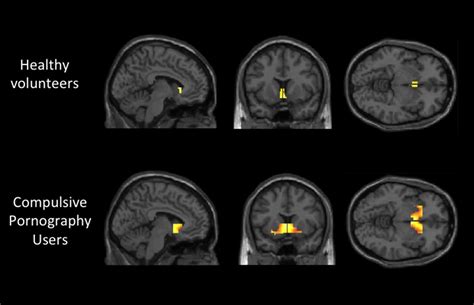

Neuroscientist On The Dark Side Of Porn Youtube